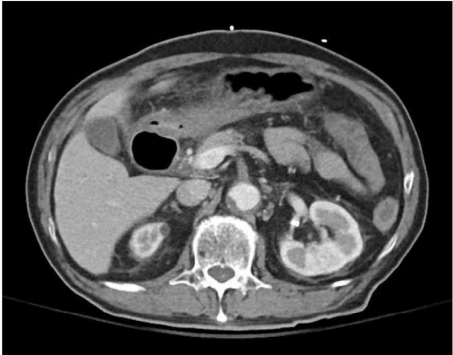

85세 남자가 4시간 전부터 혈변을 본다고 병원에 왔다. 30년 전부터 고혈압, 당뇨병으로 진단받고 약물을 복용 중이다. 식후 갑작스러운 복통이 생겼고 1시간 뒤 점액이 섞인 혈변을 보았다고 한다. 혈압 150/90 mmHg, 맥박 96회/분, 호흡 22회/분, 체온 37.9°C이다. 배는 팽만하고, 배 전체에 압통이 있으나 반동압통은 없다. 복부 컴퓨터단층촬영 사진이다. 진단은?

CT: Ascending colon wall thickening with nearby fluid collection, SMA stenosis/occlusion

고혈압 및 당뇨 기저질환을 가진 고령환자에게서 급성 복통 및 혈변이 발생하였으며, CT상 SMA stenosis/occlusion이 확인되므로 ischemic colitis로 진단한다.

• 혈액검사 결과 leukocytosis 및 CRP/ESR elevation 소견은 환자에게 염증성 병변이 발생했음을 시사하며, 복부 CT상 SMA의 near-total occlusion이 확인되고, SMA가 주된 혈류를 담당하는 ascending colon의 wall thickening과 주변 fluid collection이 허혈대장염이 적절한 진단명일 가능성이 높다.